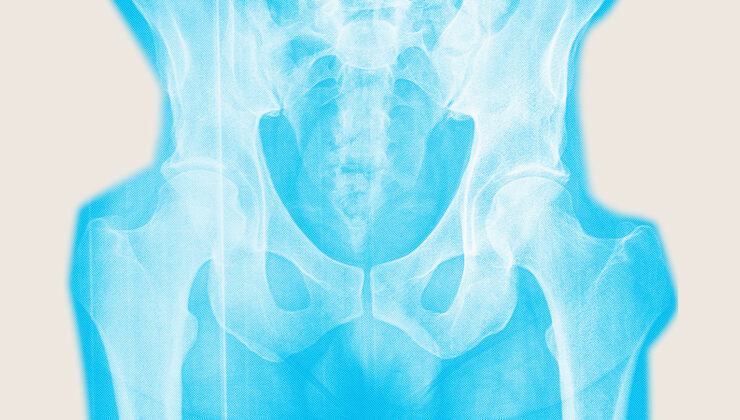

Osteoporoz ile zayıflatılan kemiklerin kırılma olasılığı daha yüksektir, bu da zayıflatıcı ve hatta ölümcül olabilir. Kalça kırıkları özellikle yıkıcıdır. İnsanların yaklaşık yüzde 20’si Kalça kırığı bir yıl içinde öl. Hayatta kalanların sadece yüzde 40 ila 60’ının Fraksiyon öncesi hareketliliklerini geri kazan. Kalan fiziksel sınırlamalar yaşam kalitesini bozar.

Kemik kaybı gerçekten menopoz etrafında gidiyor. Son adet döneminden önceki yıla başlayarak ve yaklaşık iki yıl sonra, Kemik yoğunluğu ortalama yıl yaklaşık yüzde 2 düşer östrojendeki düşüş nedeniyle. Bundan sonra kemik kaybı daha yavaş devam eder.